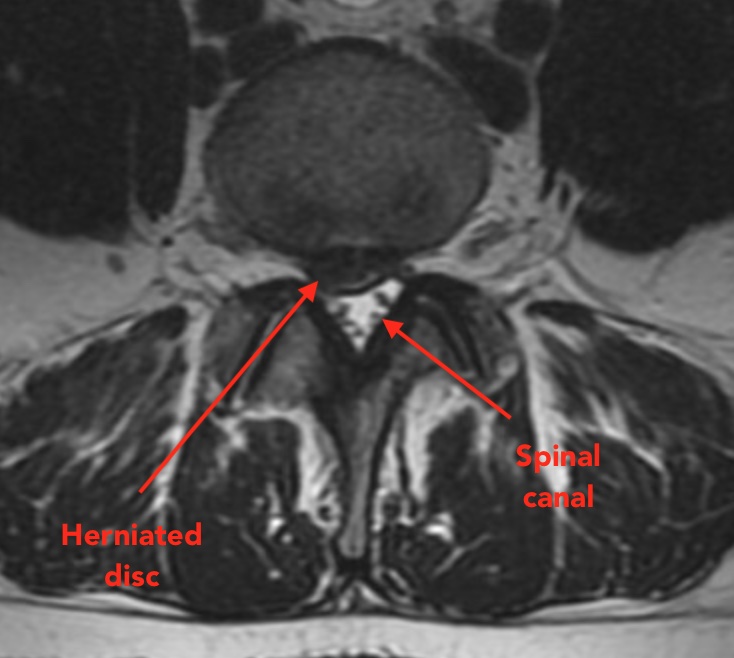

Spinal nerve roots can become irritated or compressed by protruding disc material, or narrowing of the spinal canal or passageways for the nerves to exit the spine.

Epidural steroid injections are performed under x-ray guidance, and use a small needle to access the tissue layer that lies between the protruding disc material, or narrowed vertebral bones, and the nerve root sleeves. This is called the "epidural space" because it is outside the "dura", or protective sheath that contains the nerves and spinal cord.